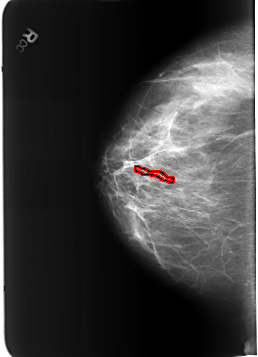

FILE: B_3212_1.LEFT_MLO.OVERLAY

TOTAL_ABNORMALITIES 1

ABNORMALITY 1

LESION_TYPE CALCIFICATION TYPE VASCULAR DISTRIBUTION N/A

ASSESSMENT 2

SUBTLETY 3

PATHOLOGY BENIGN_WITHOUT_CALLBACK

TOTAL_OUTLINES 1

BOUNDARY